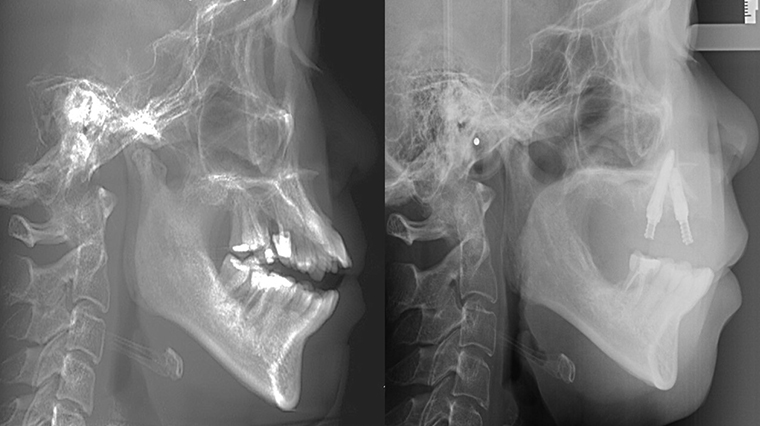

▲治療前,前牙嚴重開咬且上顎牙均有嚴重牙周病,導致上唇外暴。(左);治療後,利用植牙讓上顎前牙內收排列,使上唇恢復自然閉合,臉部輪廓自然美觀(右)。(圖/台北慈濟醫院提供)